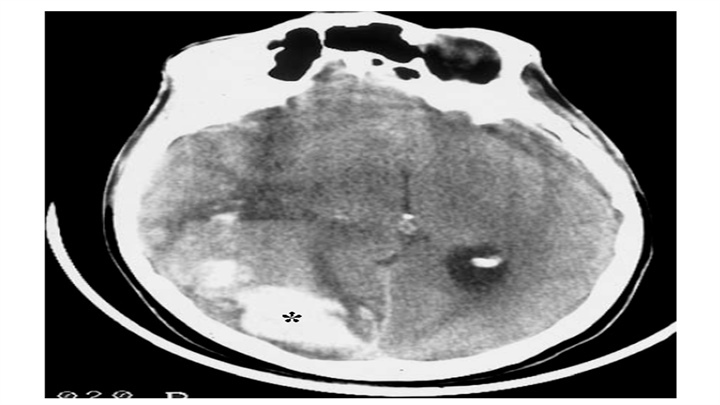

IPH随时间的演变。CT通常用于IPH随访中。上图为脑血肿患者在中风后数小时内的CT,注意病灶位置深,锯齿状边缘和小卫星灶的存在;中间图为14天后的CT,血肿体积缩小,密度减低,而周围水肿加重。下图为三个月后CT,病变被不规则低密度腔所取代,负占位效应,同侧侧脑室轻微扩张。